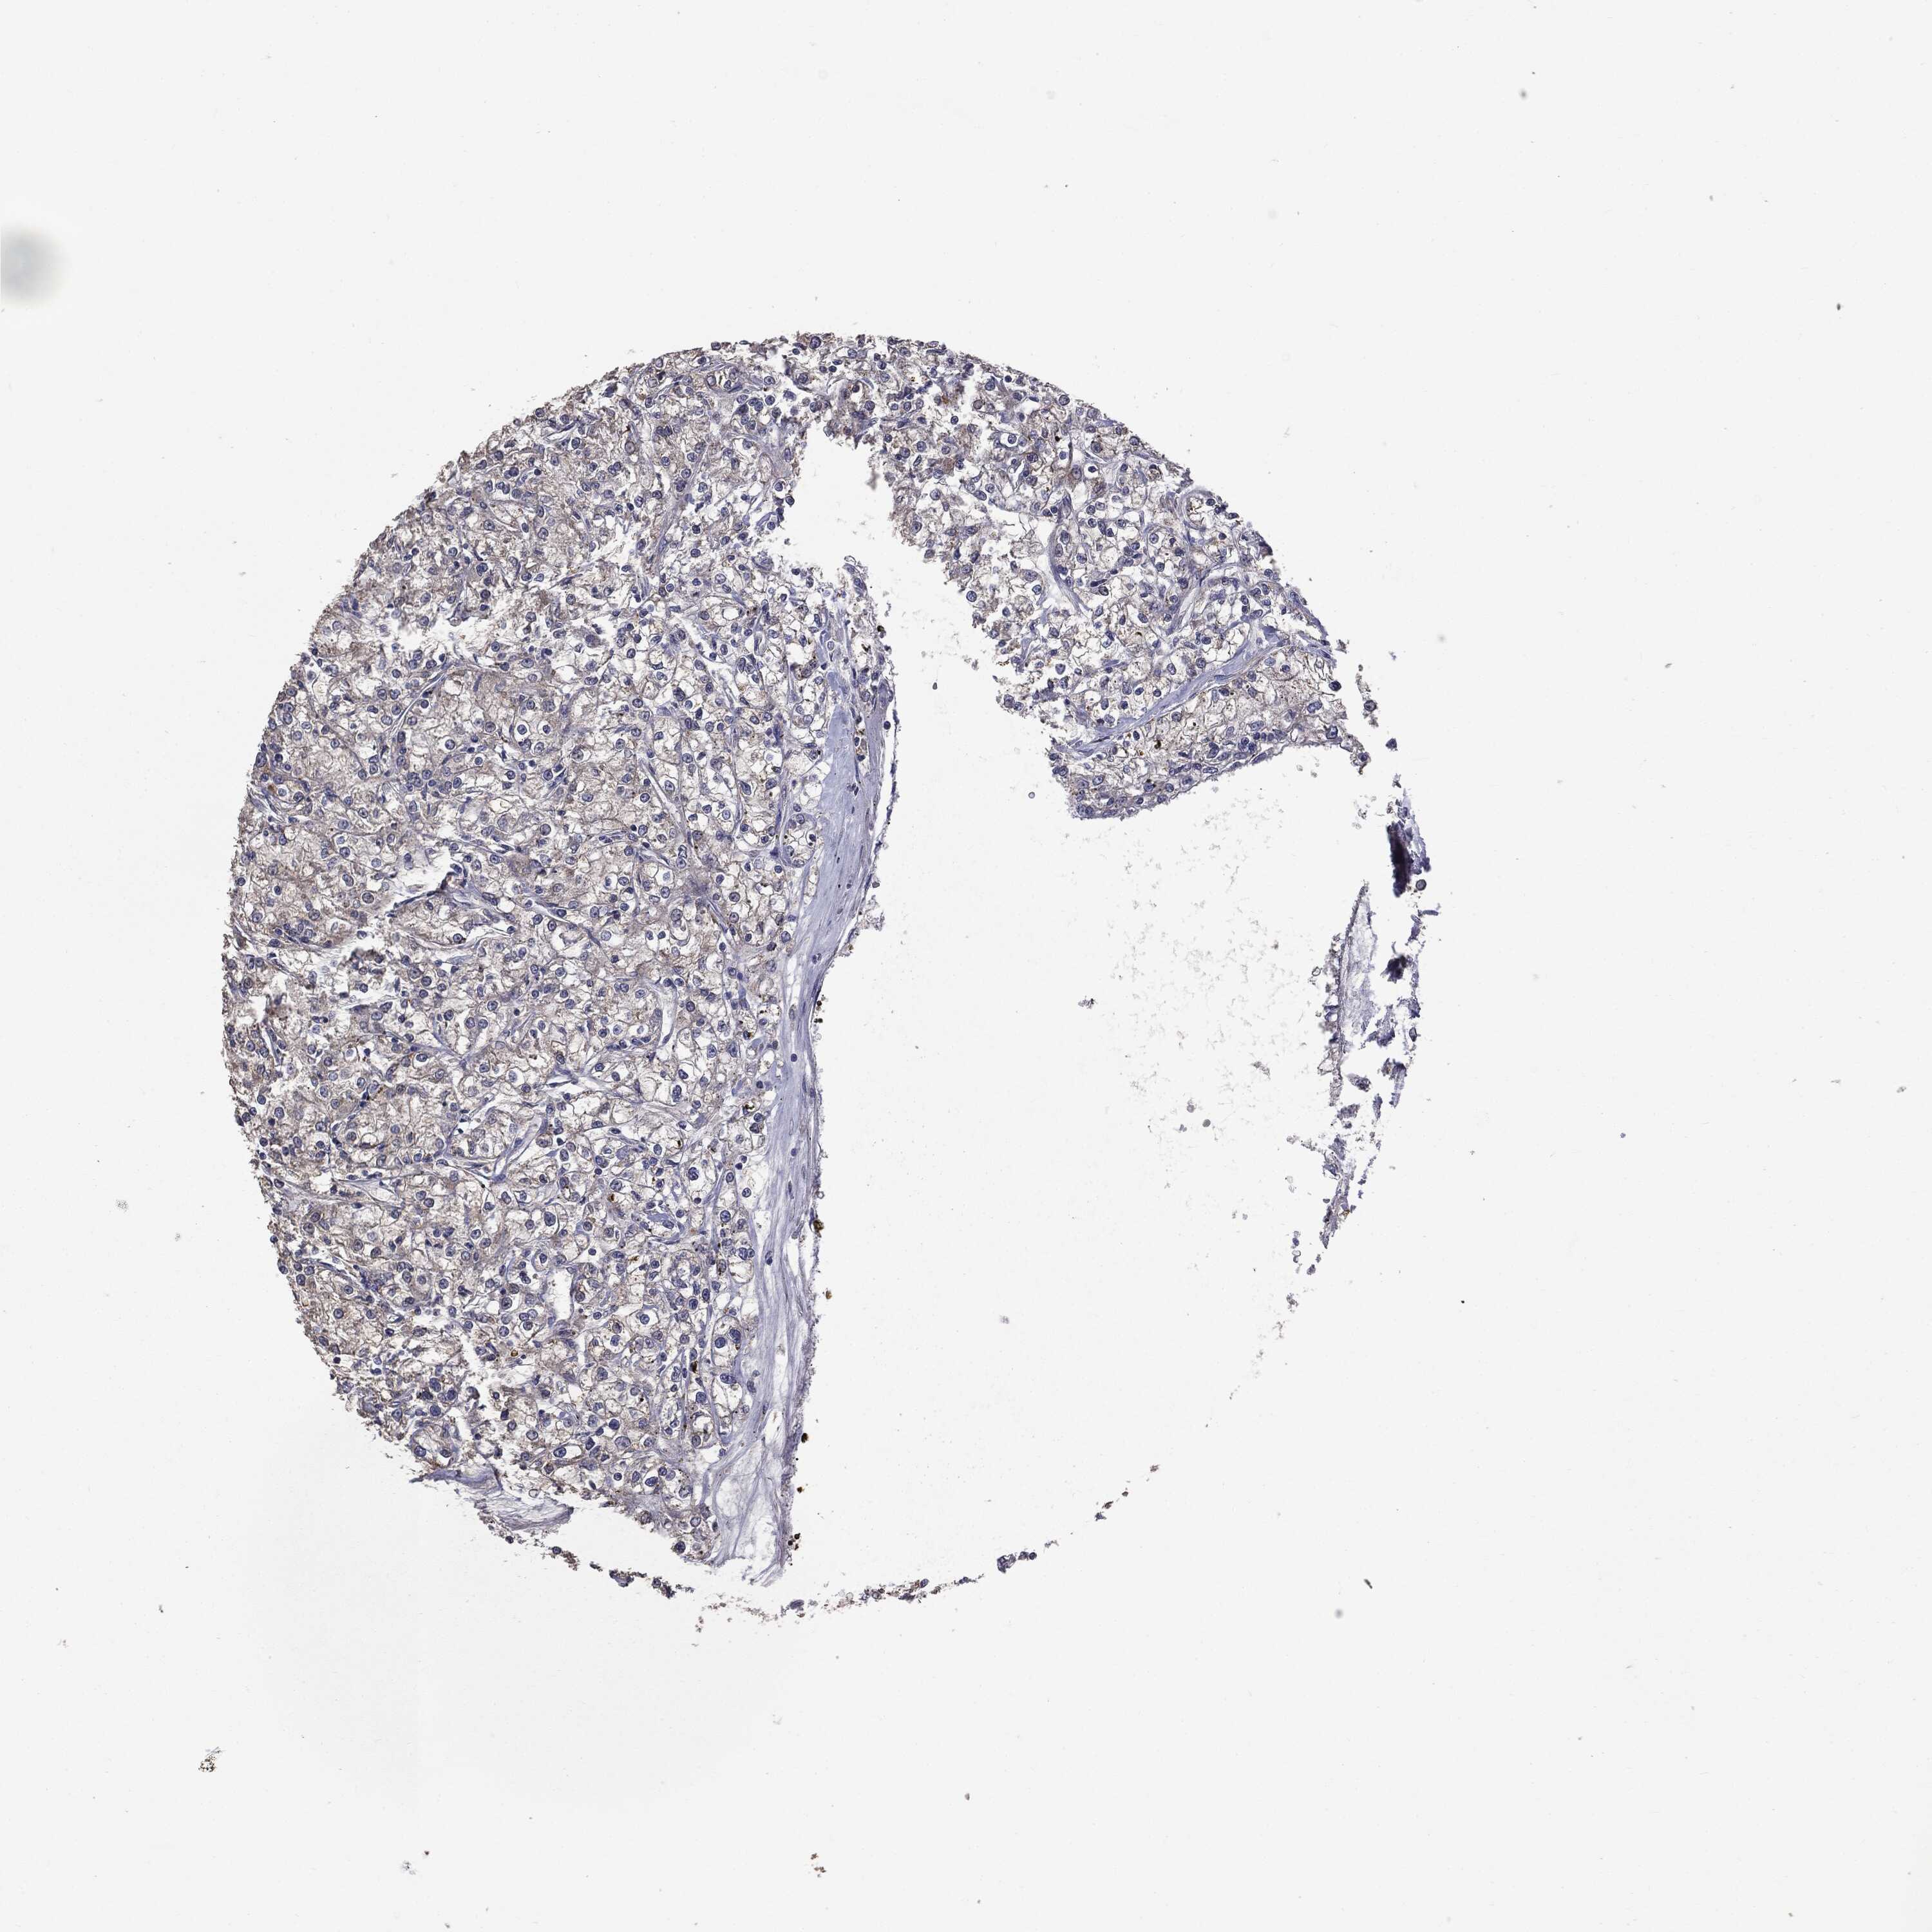

KIDNEY RENAL PAPILLARY CELL CARCINOMA (TCGA) - Interactive survival scatter ploti

The Survival Scatter plot shows the clinical status (i.e. dead or alive) for all individuals in the patient cohort, based on the same data that underlies the corresponding Kaplan-Meier plots. Patients that are alive at last time for follow-up are shown in blue and patients who have died during the study are shown in red.

The x-axis shows the expression levels (FPKM) of the investigated gene in the tumor tissue at the time of diagnosis. The y-axis shows the follow-up time after diagnosis (years). Both axes are complimented with kernel density curves demonstrating the data density over the axes. The top density plot shows the expression levels (FPKM) distribution among dead (red) and alive patients (blue). The right density plot shows the data density of the survived years of dead patients with high and low expression levels respectively, stratified using the cutoff indicated by the vertical dashed line through the Survival Scatter plot. This cutoff is automatically defined based on the FPKM cutoff that minimizes the p-score. The cutoff can be changed by dragging the vertical line or by entering a cutoff value in the square labeled "Current cut-off".

Under the Survival Scatter plot the p-score landscape (black curve; left axis) is shown together with dead median separation (red curve; right axis). Dead median separation is the difference in median mRNA expression between patients who have died with high and low expression, respectively. It is calculated as follows: median FPKM expression of dead patients with high expression - median FPKM expression of dead patients with low expression. This is intended to aid the user in visually exploring custom cutoffs and the associated p-scores and dead median separation.

Individual patient data is displayed and can be filtered by clicking on one or more of the category buttons on the top of the page. Categories describing expression level and patient information include: high, low, alive, dead, female, male and tumor stages. The scale of the x-axis can be toggled between linear and log-scale by clicking on the "x log" button. Mouse-over function shows TCGA ID, patient information and mRNA expression (FPKM) for each patient.

& Survival analysisi

Kaplan-Meier plots summarize results from analysis of correlation between mRNA expression level and patient survival. Patients were divided based on level of expression into one of the two groups "low" (under cut off) or "high" (over cut off). X-axis shows time for survival (years) and y-axis shows the probability of survival, where 1.0 corresponds to 100 percent.

MTOR is not prognostic in Kidney Renal Papillary Cell Carcinoma (TCGA)

Best expression cut offi

Based on the FPKM value of each gene, patients were classified into two groups and association between prognosis (survival) and gene expression (FPKM) was examined. The best expression cut-off refers the FPKM value that yields maximal difference with regard to survival between the two groups at the lowest log-rank P-value. Best expression cut-off was selected based on survival analysis .

When clicking on this number, the vertical dashed line indicating cut-off, the interactive survival plot, and the Kaplan-Meier curve will be adjusted to show results based on the best expression cut-off.

: 15.26